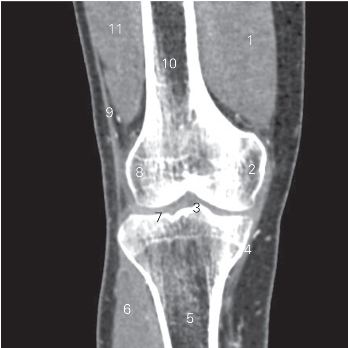

图5-22 经胫骨髁间隆起的冠状断层CT图像(软组织窗)

1 股内侧肌 vastus medialis 2 股骨内侧髁 medial condyle of femur

3 胫骨髁间隆起 intercondylar eminence of tibia

4 胫侧副韧带 tibial collateral ligament

5 胫骨 tibia 6 趾长伸肌 extensor digitorum longus

7 胫骨平台 tibial plateau 8 股骨外侧髁 lateral condyle of femur

9 髂胫束 iliotibial tract 10 股骨 femur

11 股外侧肌 vastus lateralis